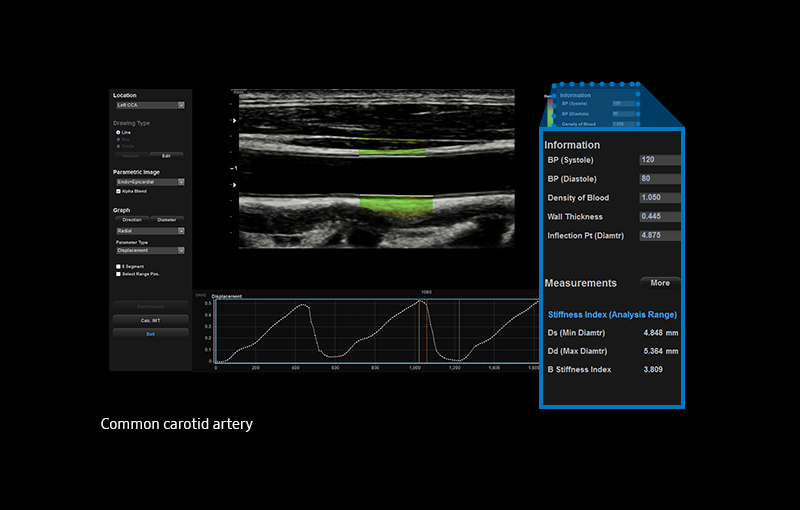

Arterial Analysis™ ¹

Detect functional changes of cardiovascular vessels

Arterial Analysis™ ¹ detects functional changes of vessels, providing measurement values such as the stiffness, intima-media thickness and pulse wave velocity of the common carotid artery. Since the functional changes occur before morphological changes, this technology supports the early detection of cardiovascular disease.